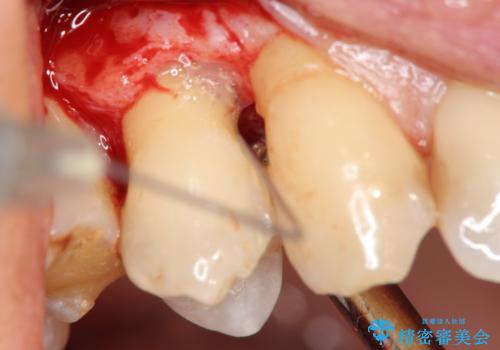

部分矯正を含む 歯周病治療 (再生治療・歯周ポケット除去・MTM・連結補綴)

検査の結果、強い歯ぎしりによる歯の周囲の骨の吸収が認められたため歯槽骨の再生・歯周ポケットの除去・力に対抗する連結補綴・補綴前処置としての小矯正を計画します。

今回連結補綴を行うにあたり、歯周病の問題を解決するために再生療法・歯周ポケット除去手術を、またより歯の神経を保存し力に対抗できる環境を整えるために小矯正を行い精度の高いメタルボンドクラウンを製作することができました。